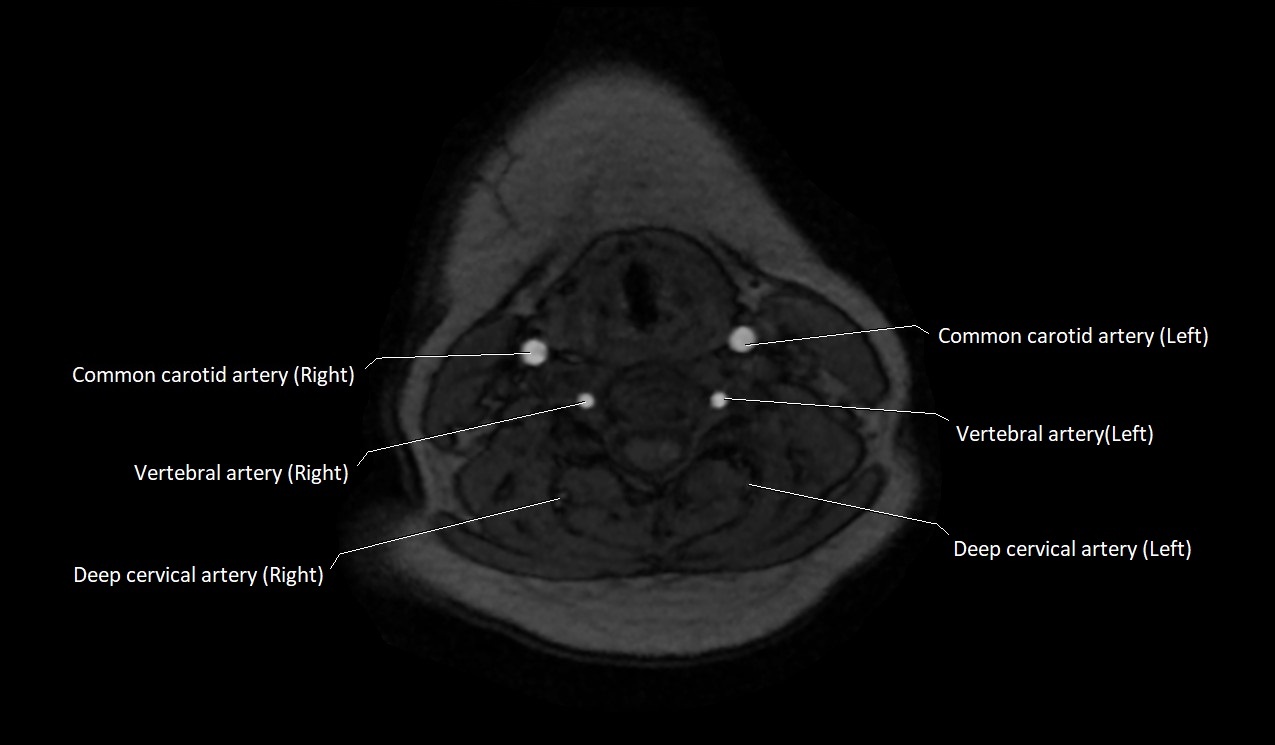

MRI images

image